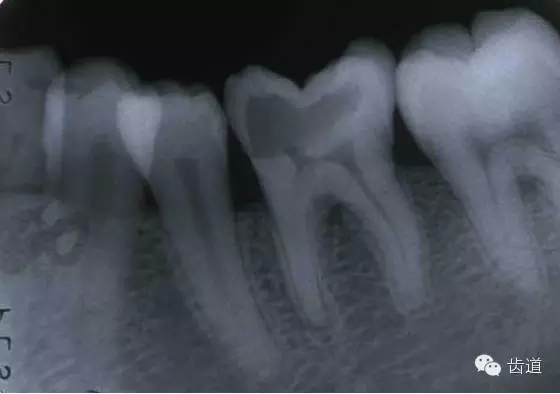

左上5牙頸部側(cè)穿

左下6底穿

左上6底穿